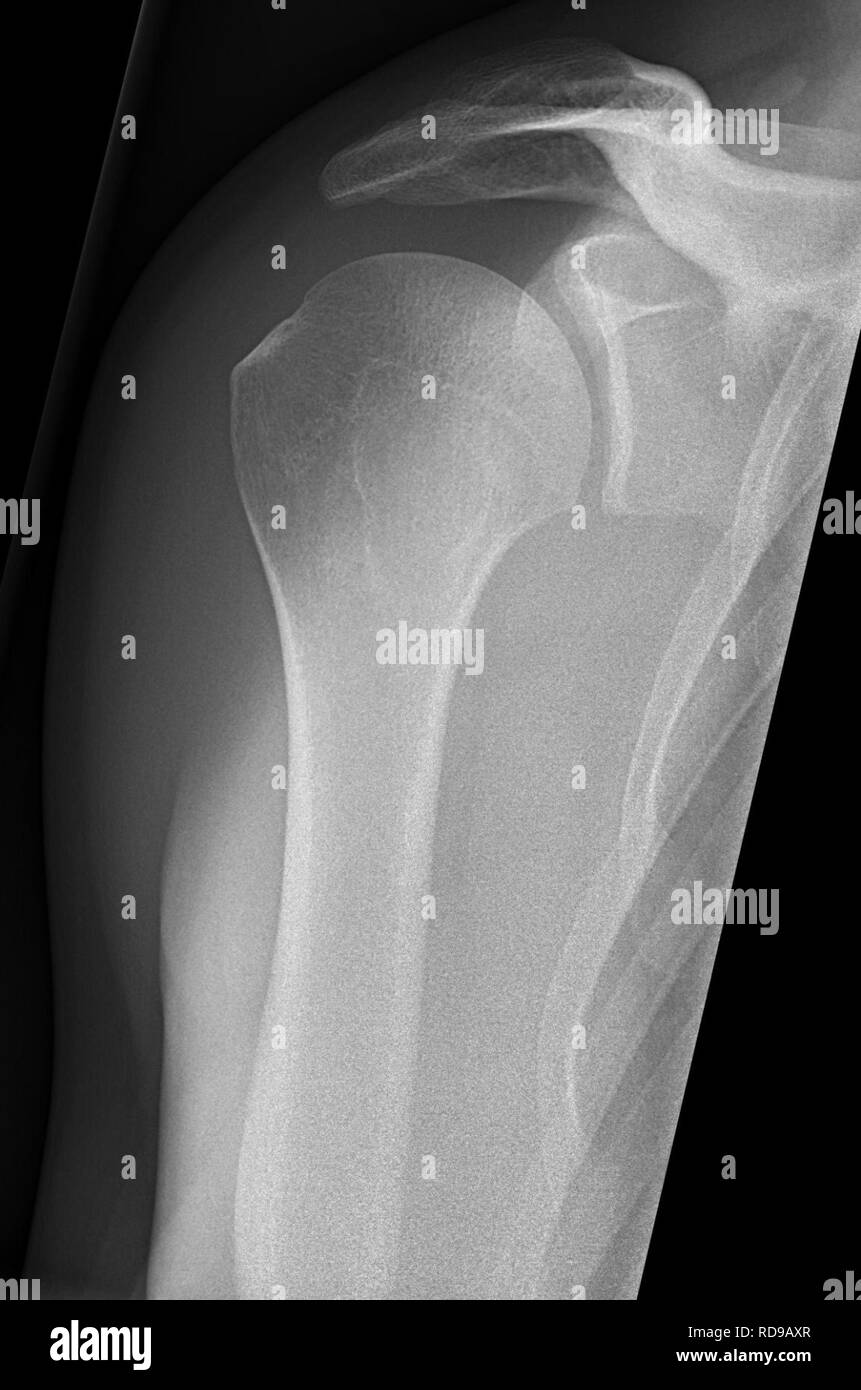

the shoulder ap glenoid view also known as a true ap or a 'grashey view ' is an additional projection to the two view shoulder series. The body has to be rotated about 30 to 45 degrees towards the shoulder to be imaged, and the standing or sitting patient. Mri is best for evaluating soft tissue structures and evaluating bone contusions or trabelcular. the shoulder series is fundamentally composed of two orthogonal views of the glenohumeral joint including the. The overlap between the humerus and the glenoid seen on the ap view is removed in the grashey projection by rotating the patient posteriorly or angling the beam laterally. glenohumeral “true” ap (grashey) view. The true ap view, or grashey view ( fig. The projection is used to assess the.

Grashey X Ray Labeled glenohumeral “true” ap (grashey) view. The projection is used to assess the. The overlap between the humerus and the glenoid seen on the ap view is removed in the grashey projection by rotating the patient posteriorly or angling the beam laterally. The true ap view, or grashey view ( fig. the shoulder series is fundamentally composed of two orthogonal views of the glenohumeral joint including the. the shoulder ap glenoid view also known as a true ap or a 'grashey view ' is an additional projection to the two view shoulder series. The body has to be rotated about 30 to 45 degrees towards the shoulder to be imaged, and the standing or sitting patient. Mri is best for evaluating soft tissue structures and evaluating bone contusions or trabelcular. glenohumeral “true” ap (grashey) view.